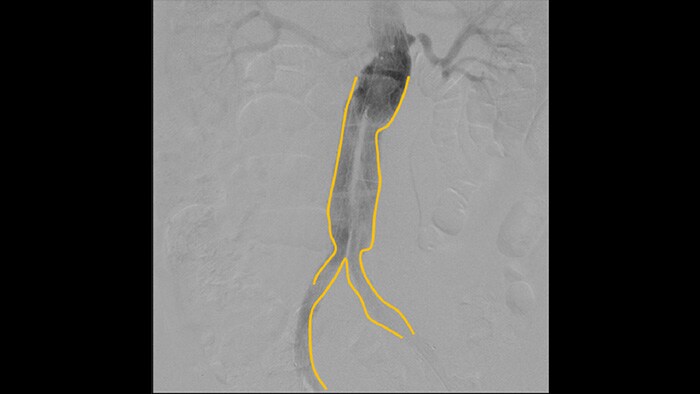

With the Philips Zenition mobile C-arm, Dr. Vila is obtaining outstanding high-quality images that allow him to perform most vascular procedures at the low dose setting.

With the Zenition, our DSA image quality has improved greatly. We no longer see a grainy image. We just see a very clear image."

Digital subtraction angiography (DSA) is used in interventional vascular procedures to clearly visualise blood vessels by removing structures that can obscure vessel visibility. Roadmap fluoroscopy overlays a previously acquired subtracted contrast image on the live fluoroscopy, allowing you to track a device without reinjecting contrast.

Use the Outlining tool to easily mark a bifurcation or side branches by simply drawing on the monitor of the Mobile Viewing Station with your finger or an externally connected mouse.